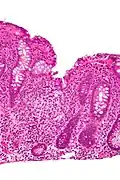

Cryptitis. H&E stain. -